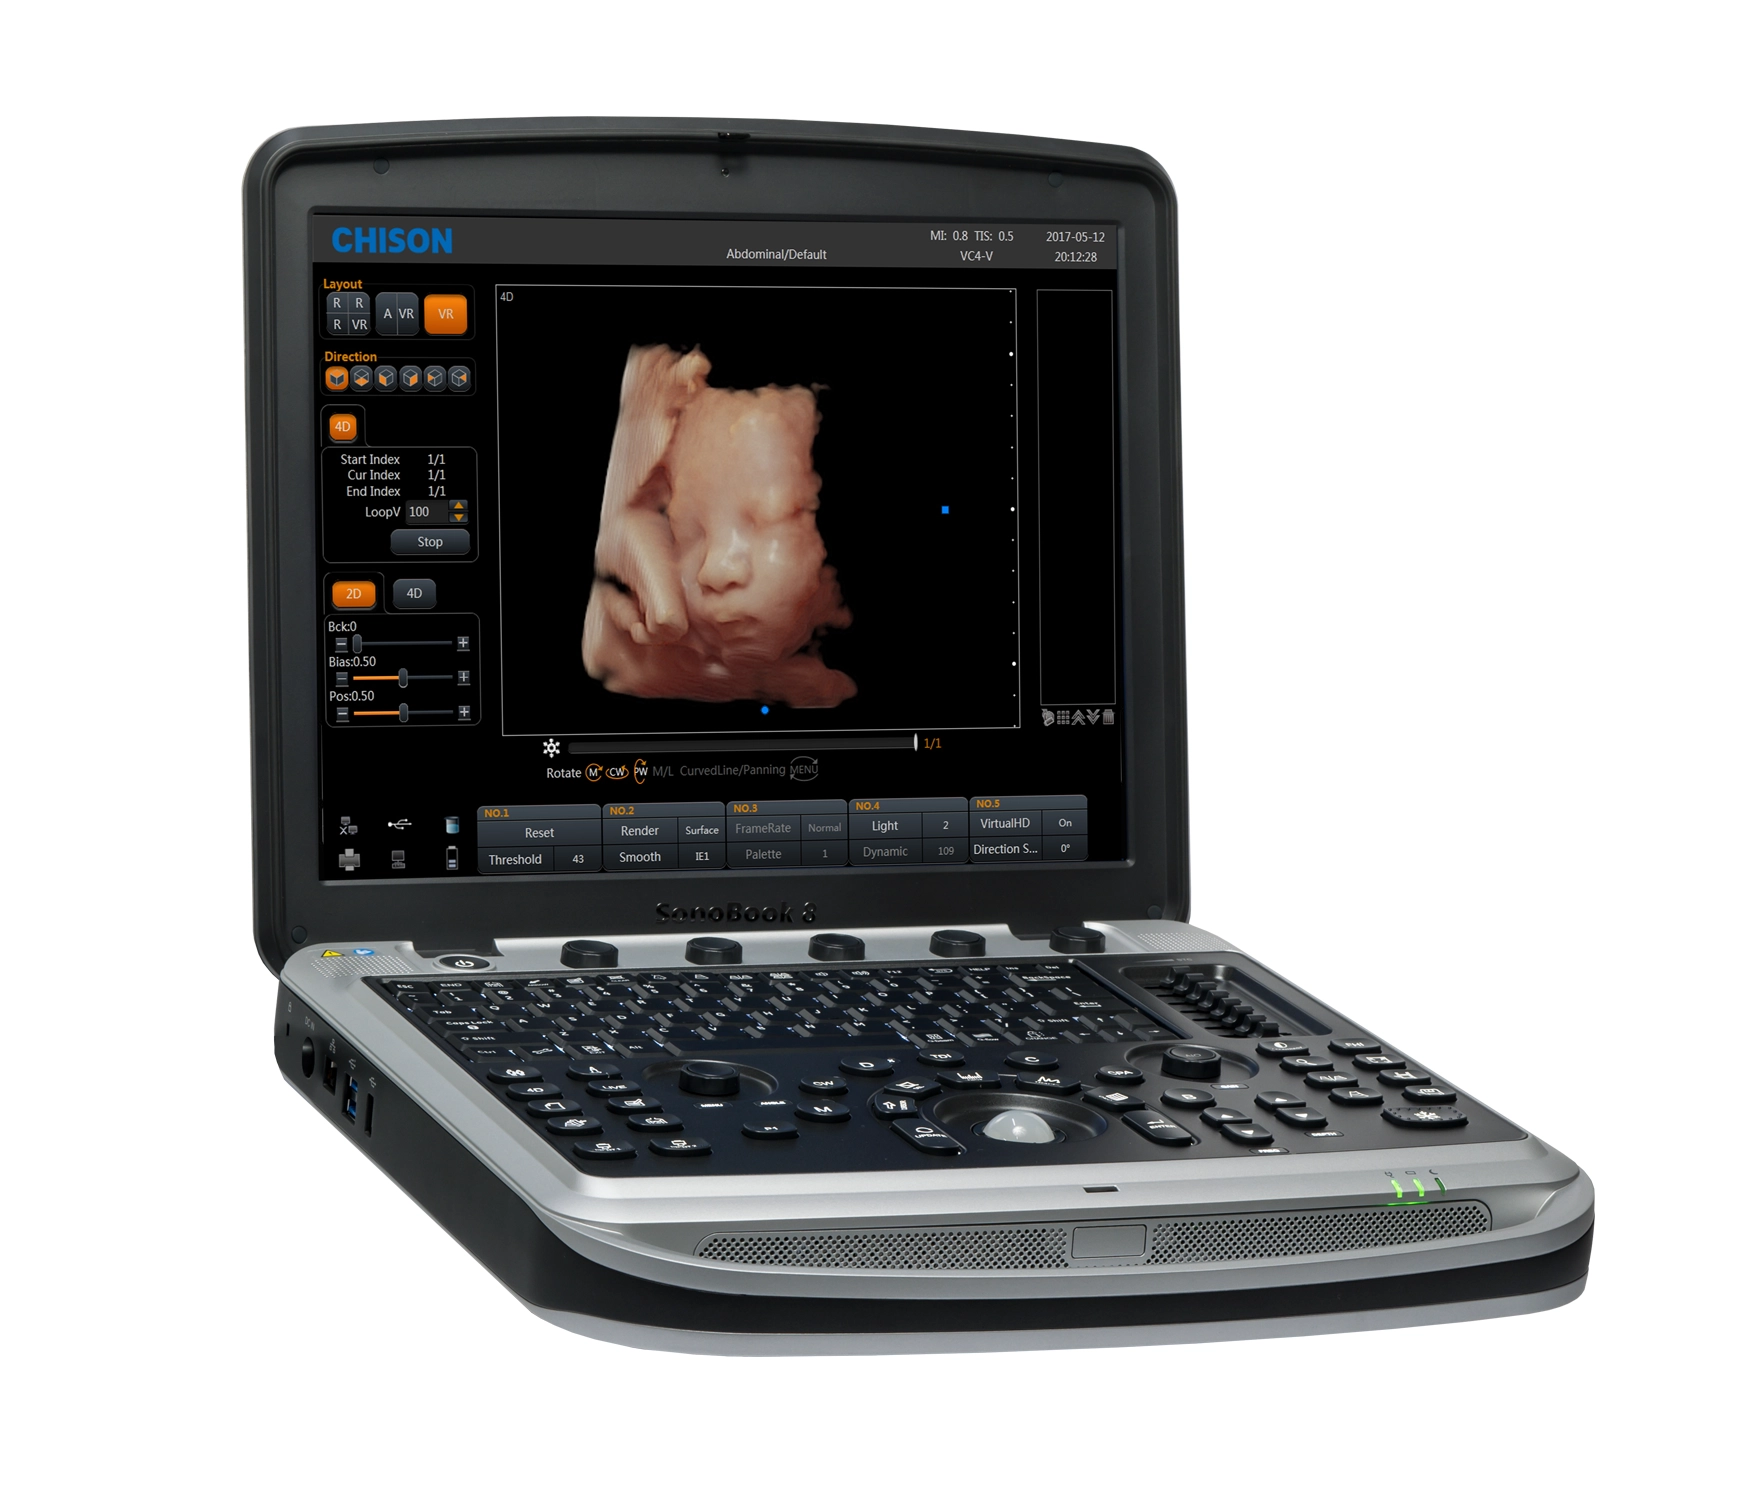

Tenemos oficinas corporativas en CDMX, GUADALAJARA, MONTERREY, CHIHUAHUA ,en ellas encontrarás salas de exhibición con equipo de Ultrasonido, Quirófano, Laparoscopía, Endoscopía, Neonatología y Aparatología Estetica.